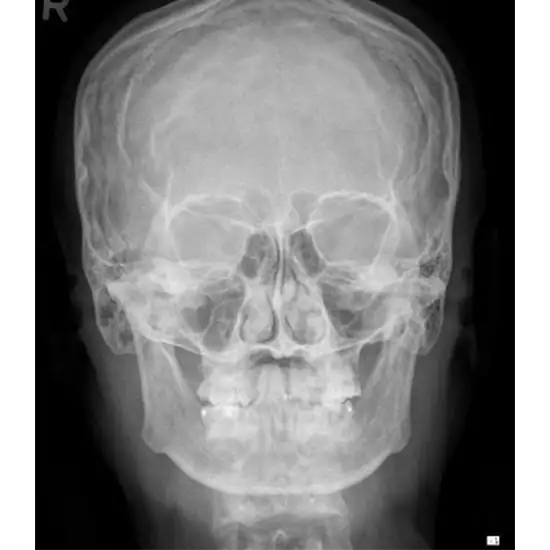

The X-ray of the Caldwell view of the skull is a test to visualize the paranasal sinuses, namely the frontal sinus and the surrounding soft tissues (skin and muscles).

The doctor prescribes this test to detect a nasal sinus's chronic inflammation and evaluate any blockage in the sinus region.

• To determine the presence of persistent frontal sinusitis (inflammation of a nasal sinus)

• To identify osteoma (localized tumor) in the sinus region

• To examine any obstruction in the sinus region.